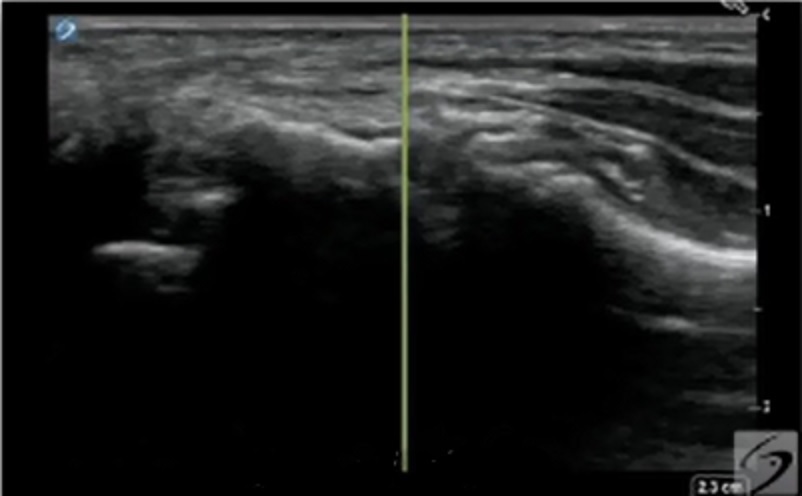

手首の第1CMC関節注射アウトオブプレーンの画像